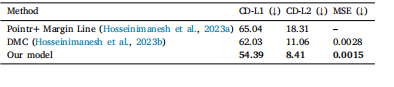

Table 1Comparison of the new model with our previous methods. Evaluation metrics are 𝐶𝐷𝐿1and 𝐶𝐷𝐿2(multiplied by 1000; lower is better) and MSE (calculated on output meshes;lower is better). Bold values indicate improvements achieved by the new model. MSEis unavailable for the Pointr+ Margin Line experiment as it is calculated on outputmeshes.

表1:新模型与我们先前方法的比较。评估指标为(CD{L1})和(CD{L2})(乘以1000;数值越低越好)以及均方误差(MSE,在输出网格上计算;数值越低越好)。加粗的值表示新模型所取得的改进。对于“Pointr + 边缘线”实验,均方误差(MSE)不可用,因为它是在输出网格上计算的,而该实验情况不适用。